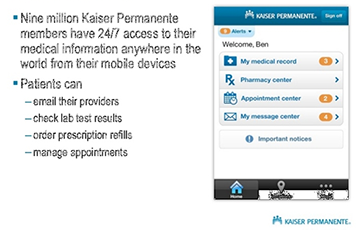

USAA ~ Safeway ~ Limited Brands ~ Macy's ~ Sears ~ Emporium ~ Nokia ~ Motorola ~ Samsung ~ LG ~ BlackBerry ~ HTC ~ Wal-Mart Stores ~ CVS ~ Best Buy ~ Rite Aid ~ Nike ~ GAP ~ J. C. Penney ~ Chevron ~ General Electric ~ AT&T ~ Hewlett-Packard ~ Bank of America Corp. ~ Citigroup ~ Berkshire Hathaway ~ International Business Machines ~ McKesson ~ Kaiser Permanente ~ Kaiser Hospitals ~ U.C.S.F ~ Stanford University School of Medicine/Medical Center ~ Sutter Healthcare ~ California Pacific Medical Center ~ San Francisco General Hospital And Medical Center ~ San Francisco VA Medical Center ~ U.S. Department of Transportation ~ U.S. Department of Homeland Security ~ Exar ~ Boeing ~ AIS ~ Siemens ~ Kaiser People Solutions ~ Cardinal Health ~ Procter & Gamble ~ UnitedHealth Group ~ Kroger ~ Marathon Oil ~ Costco Wholesale ~ Home Depot ~ Target ~ Johnson & Johnson ~ Morgan Stanley ~ State Farm Insurance ~ Dell ~ Boeing ~ Microsoft ~ Walgreen ~ United Technologies ~ Dow Chemical ~ MetLife ~ Wells Fargo ~ United Parcel Service ~ Caterpillar ~ Lowe's ~ Sears Holdings ~ Cisco Systems ~ Johnson Controls ~ FedEx ~ Intel ~ Sysco ~ Comcast ~ Coca-Cola ~ American Express ~ Aetna ~ Motorola ~ Allstate ~ Prudential Financial ~ Tyson Foods ~ Staples ~ Delta Air Lines ~ City and County of Sacramento ~ City and County of San Francisco ~ City and County Oakland ~ San Jose International Airport ~ JFK International Airport